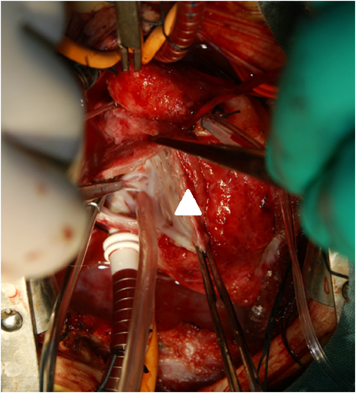

Fig. 2 Intraoperative finding of the inter-atrial septum are shown. The orifice of the coronary sinus is not visualized (arrow head)